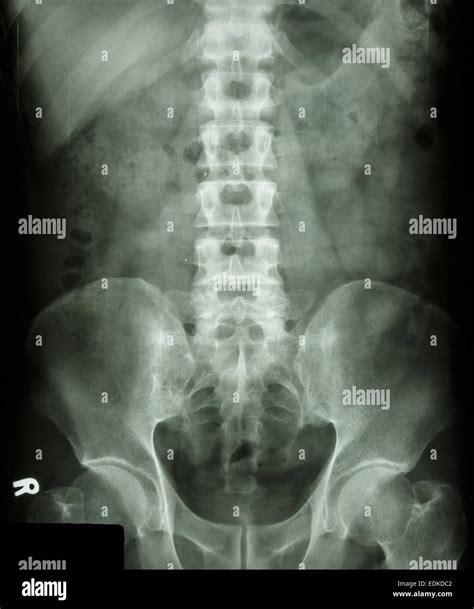

Back pain is one of the most common reasons patients visit their primary care physician. When you present with persistent or severe lower back pain, a doctor will often order an imaging study to rule out fractures, structural abnormalities, or degenerative diseases. The most frequent starting point for this diagnostic process is a Normal X Ray Ls Spine (lumbosacral spine). This basic diagnostic tool provides essential images of the lower portion of your vertebral column, allowing medical professionals to visualize bone structure and alignment. Understanding what this report means, what the radiologist is looking for, and why a "normal" result is often a positive finding is essential for managing your spinal health.

An X-ray of the lumbosacral spine is a non-invasive medical test that uses a small dose of ionizing radiation to produce pictures of the lumbar spine (the lower back) and the sacrum (the triangular bone at the base of the spine). The purpose of this imaging is to evaluate the bones for signs of injury, deformity, or disease.

When a radiologist evaluates your images and issues a report stating there is a Normal X Ray Ls Spine, it means they have not identified any acute fractures, significant tumors, or major structural dislocations that would explain your pain. It acts as a baseline, confirming that the bony architecture appears intact and stable according to standard radiological measurements.

When a technician captures these images, they generally take views from multiple angles—typically an anteroposterior (front-to-back) view and a lateral (side) view. The radiologist then meticulously reviews several specific components of your spine: